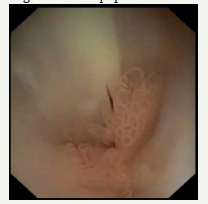

Figure 5F :Pancreaticoscopia; pseudopappilar epithelium with strands of mucus in the main pancreatic duct.